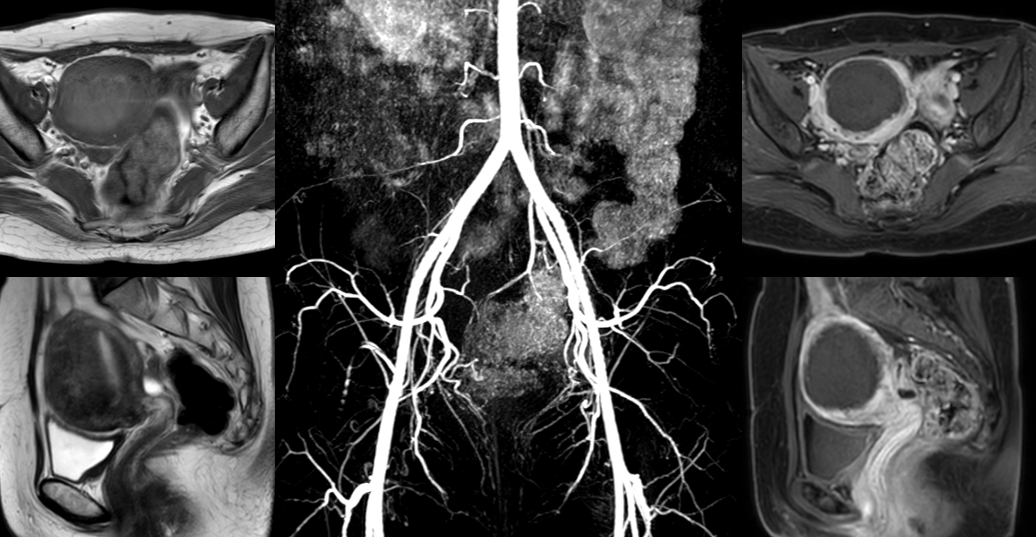

治疗后2个多月曾女士来例假,痛经消失了,月经量较术前明显减少,夜尿消失,可以一觉到天光,睡眠质量杠杠的,精力充沛。3个月后复查磁共振显示:子宫腺肌症完全灭亡(黑色区域),子宫较治疗前明显缩小(如下图)。